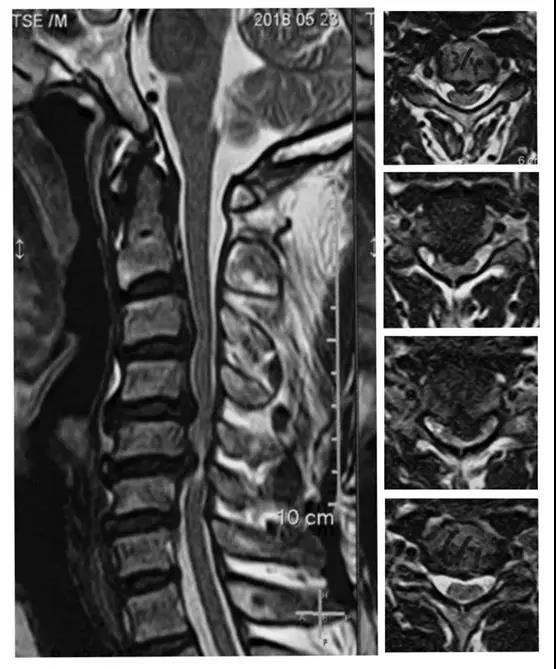

术前核磁

术后X线正侧位片